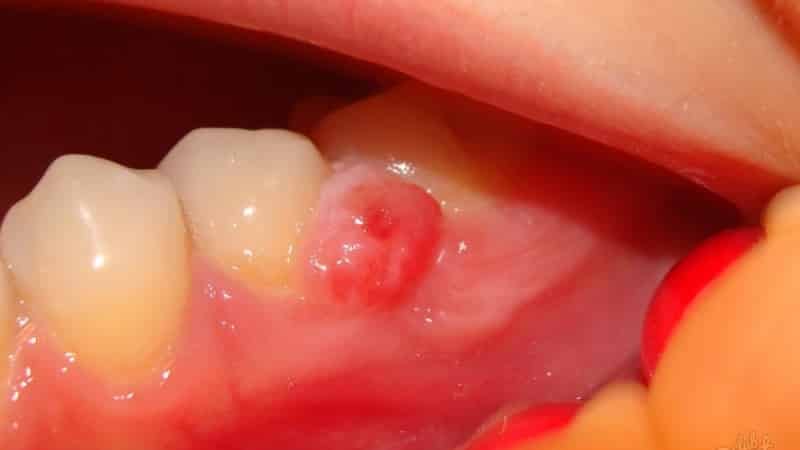

Киста в верхней и нижней челюсти является защитной реакцией организма на инфекции. Необходимо своевременно лечить различные заболевания, связанные с образованием жидкости, чтобы избежать угрозы для здоровья. Появление этого недуга может быть вызвано травмами зубов и десен, попаданием инфекций, зубными аномалиями развития, неправильным лечением зубных каналов и неправильно установленными протезными конструкциями, такими как коронки и протезы. Симптомы зависят от степени воспаления. Хроническая форма проявляется неприятными ощущениями в зубе, особенно при приеме твердой пищи, а также смещением зубов и потемнением. Увеличение кисты происходит, когда организм устает в борьбе с инфекциями, что приводит к развитию воспаления с гнойными скоплениями. В результате зуб начинает болеть, появляется сильная отечность и свищи. Пациенты также могут испытывать головные боли, слабость, общее недомогание, повышение температуры и увеличение лимфатических узлов. В таких случаях необходимо незамедлительно обратиться к специалистам.

Если киста в челюсти продолжает расти после проведенных процедур, врач может применить апикальный хирургический метод лечения. Во время этой процедуры хирург очищает содержимое кисты и удаляет инфицированный корневой кончик зуба. Затем проводится пломбирование изнутри и разрез сшивается. Если киста в нижней или верхней челюсти образуется повторно, то может потребоваться удаление зуба и установка имплантата. Современные стоматологические методы позволяют решить эту проблему, сохраняя при этом зуб.